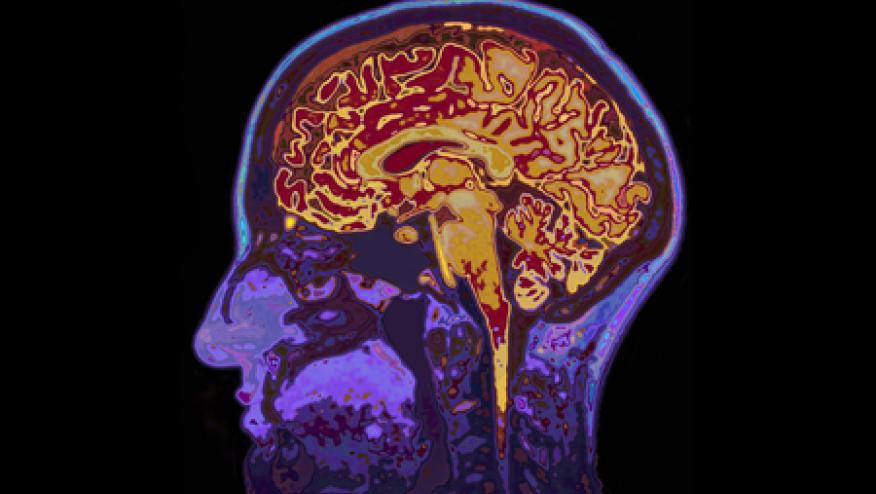

In another study (Abstract # 1646), Vassilaki and colleagues looked to identify characteristics on neuroimaging in older adults with rheumatoid arthritis. The authors found that compared to the control group, RA patients had significant differences in neuroimaging including white matter hyperintensity burden and cortical infarcts. Future studies are necessary to determine whether these cerebrovascular changes are associated with cognitive dysfunction. Furthermore, it will be important to study the impact of DMARDs on changes in neuroimaging and its association with different forms of dementia.